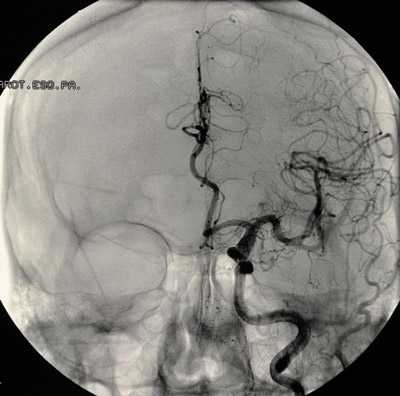

аневризма сосудов мозга на снимке

При плановых клипированиях аневризмы специалисты располагают временем для тщательного обследования пациента и подготовки его к вмешательству. В качестве консервативной терапии назначаются антигипертензивные средства, препараты, нормализующие ритм сердца при аритмиях, проводится коррекция липидного спектра при наличии отклонений.

Перед планированием операции больной подвергается всевозможным обследованиям, включая анализы крови, мочи, коагулограмму, кардиограмму и т. д., как и при других оперативных вмешательствах. Для локализации и уточнения характера сосудистого образования проводят КТ, МРТ с контрастированием, ангиографию, ультразвуковое исследование с допплером.

В случае разорвавшихся аневризм больной поступает в стационар с клиникой острого субарахноидального или внутримозгового кровоизлияния и направляется в нейрохирургическое отделение, времени на обследования фактически нет, поэтому приходится ограничиваться минимумом, позволяющим определиться с расположением мальформации.